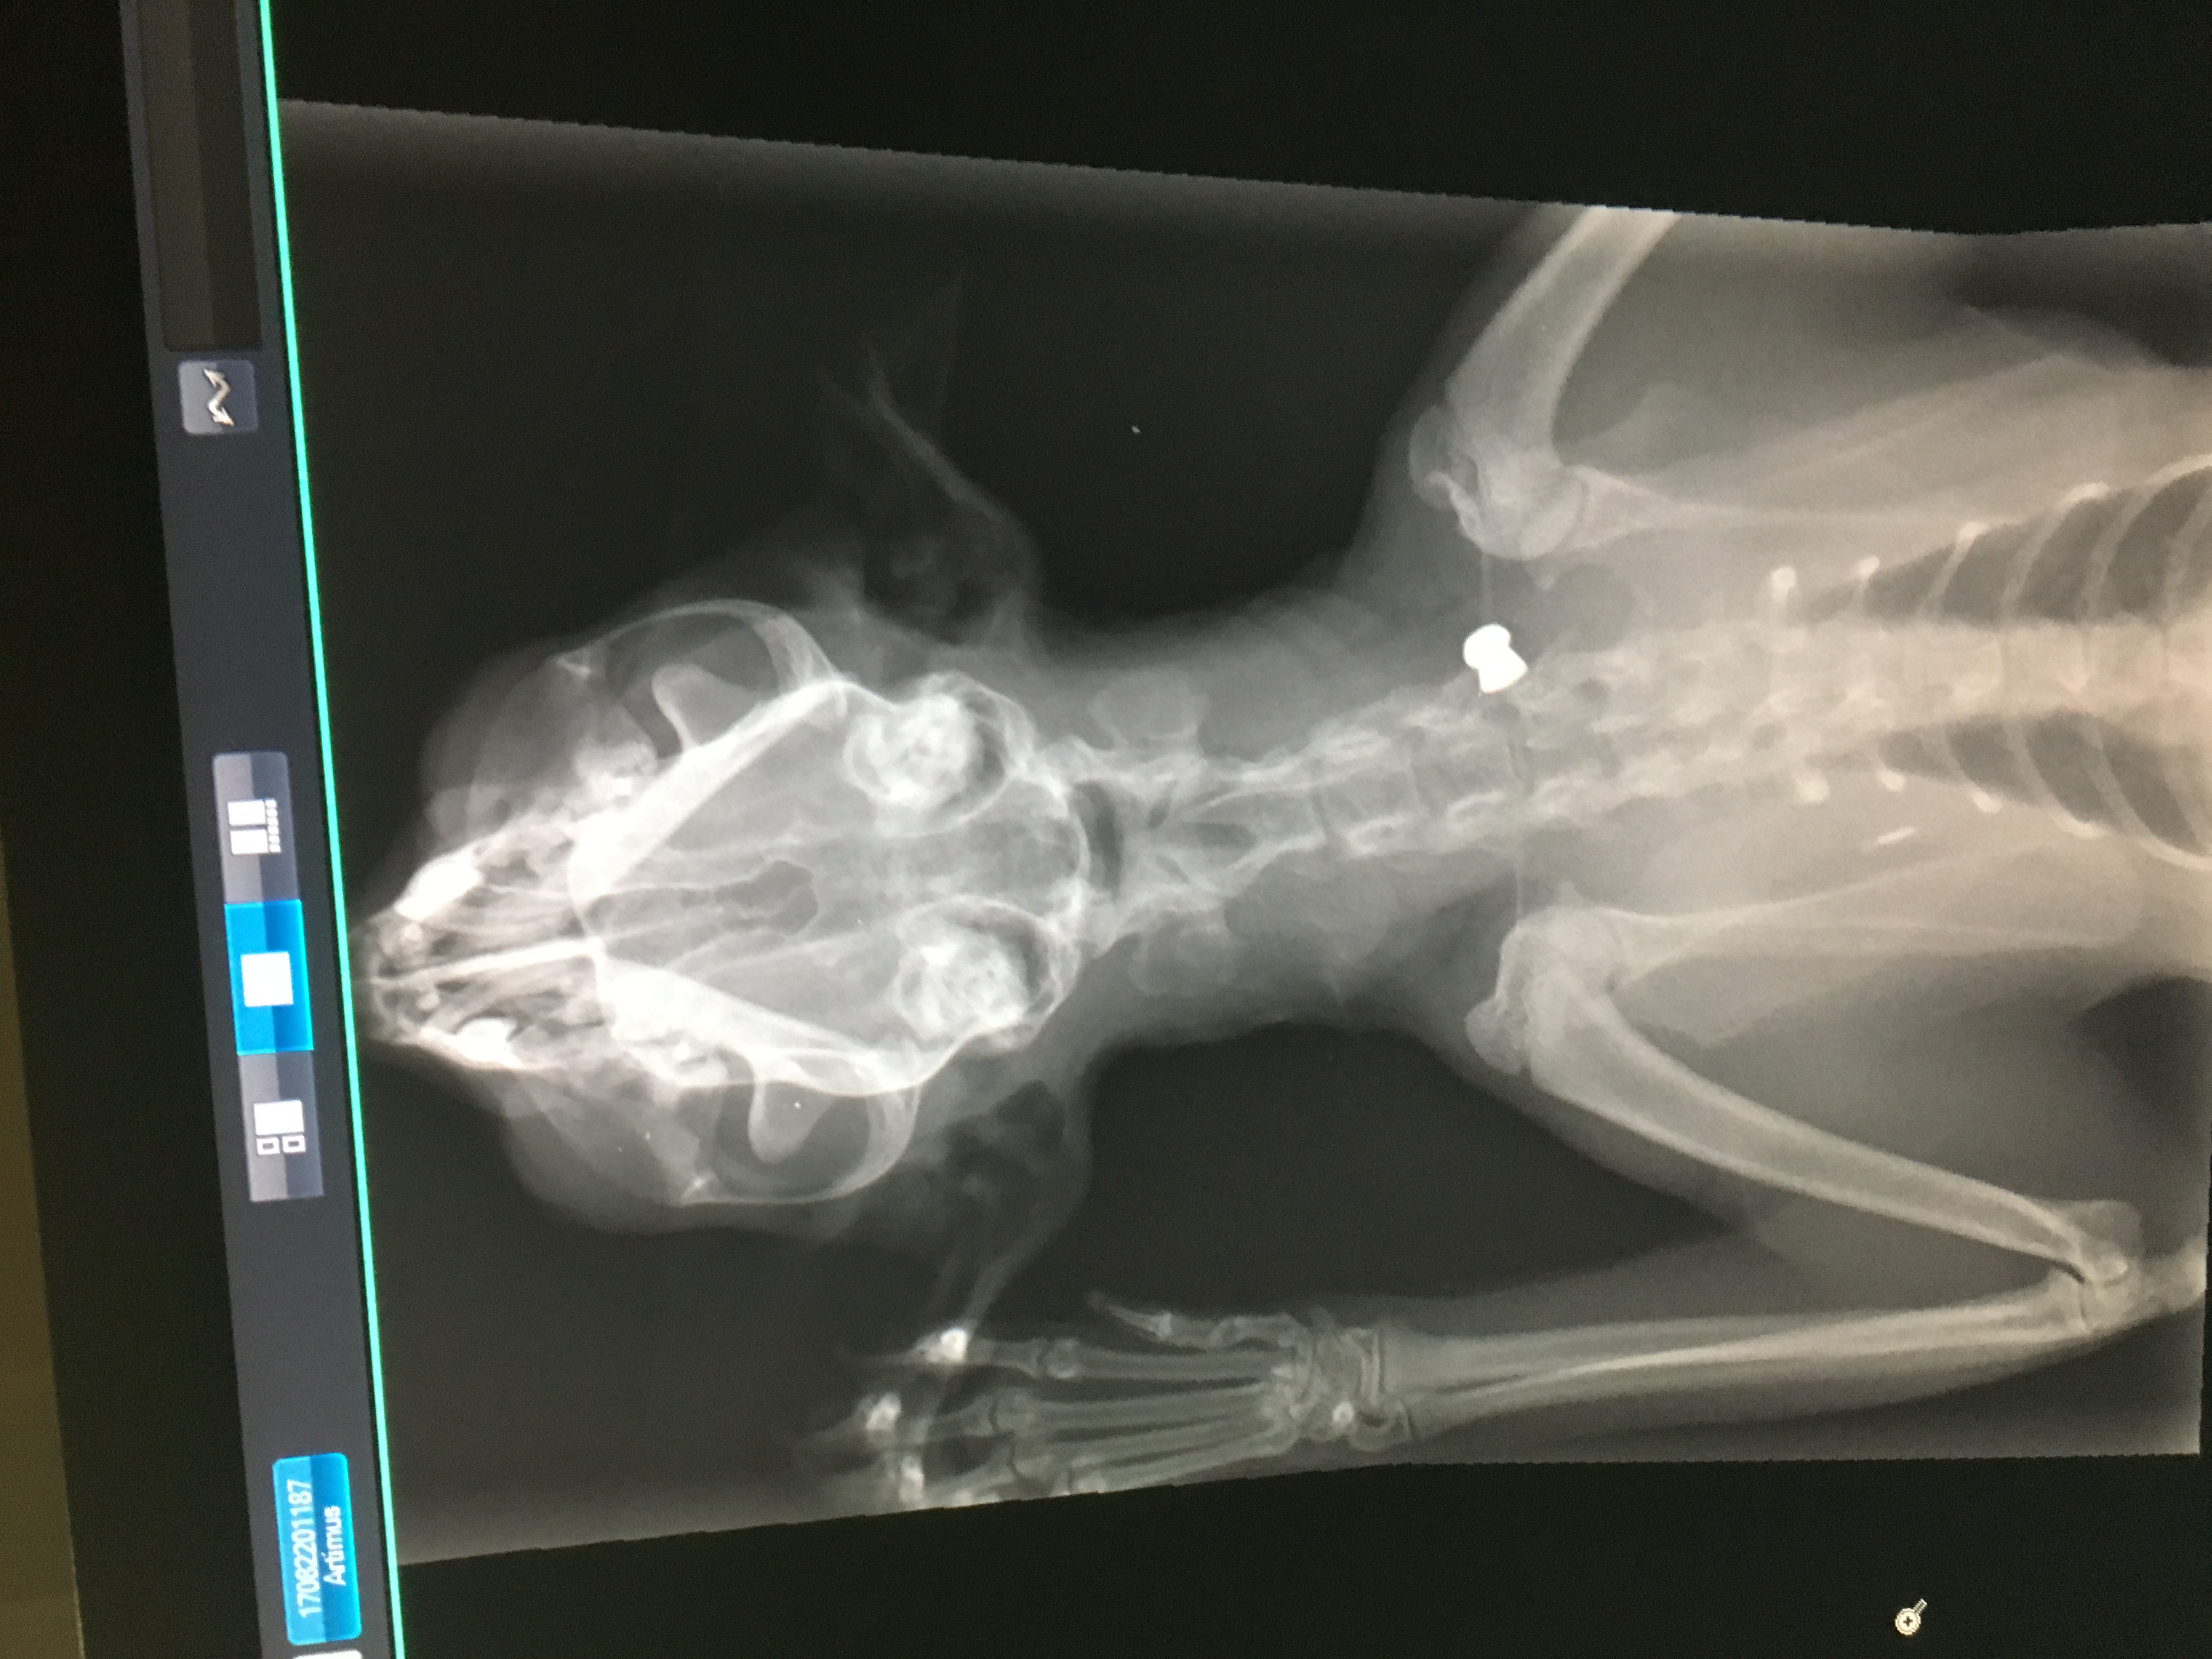

This is my kitten Artie. On Monday 21st August he was shot in the neck with an air rifle. The pellet has hit Artie's spinal cord. This has paralised his whole right side of his body. With surgery the pellet can be removed and he can begin his recovery, allowing him to eventually walk again. Unfortunately his insurance and the little money me and my fiance had towards our wedding fund has only covered the inital costs for the x-rays and CT scan. We now need more money to cover the surgery costs. Artie is our baby and a massive part of our lives (he even helped me with the proposal). It is his first birthday on 3rd September. It would mean so much if anyone could help us bring our fur baby home.